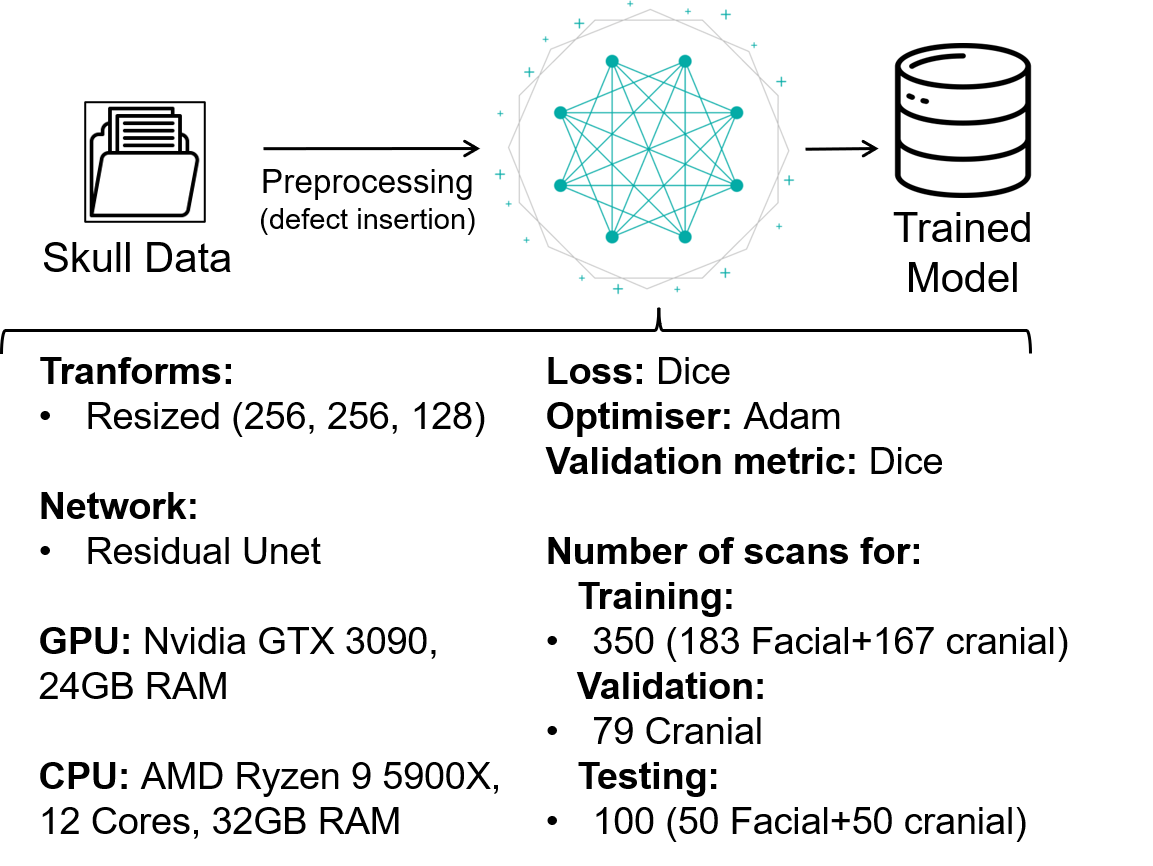

The MONAI framework is optimised for the use of Neuroimaging Informatics Technology Initiative (NIfTI) files due to the integration of the Nibabel [12] library, which makes it easier to use NIfTI files. For this reason, it was necessary to first convert the dataset (which are available in the NRRD file format [13]) to the NIfTI format. Note that even though NIfTI is a common format in medical imaging, MONAI’s image loader can also directly work with NRRD files. There are several tools that can perform this conversion. We chose to use the Python library Visualization ToolKit (VTK) to perform this conversion [14]. Then, the MONAI network is used to train the model on the converted dataset. The final output is the trained model, as shown in Figure 2.

II-C Data Resizing and Model Configurations

II-D Model Training